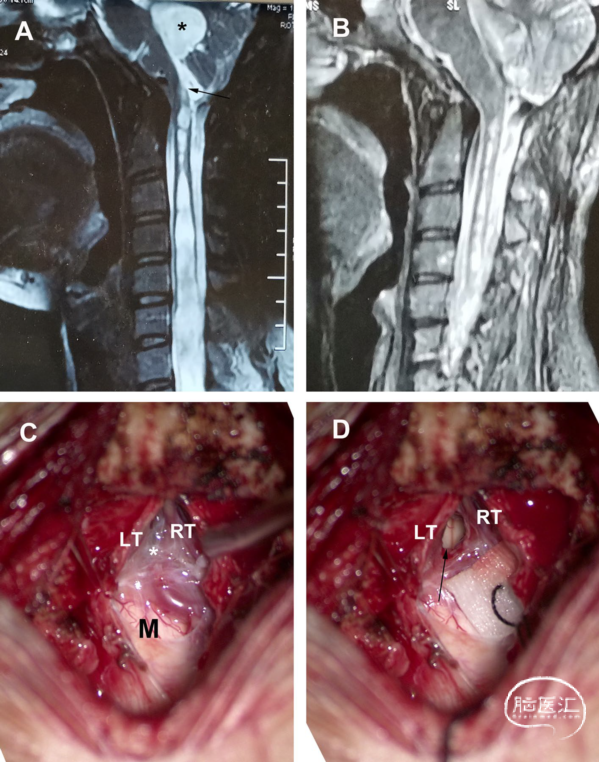

男性,68岁,有10年的双上肢麻木和无力病史。术前MRI显示颈胸段SM伴第四脑室扩张。硬膜内手术显示,扁桃体下坠到延髓蛛网膜粘连(星号)并覆盖在Magendie孔上。分离和切除部分粘连蛛网膜。术后MRI显示,SM的大小显著减小。术后症状部分缓解(图2)。

图2. 经典交通型CM-SM病例。A. 术前MRI-T2加权矢状位成像。第四脑室扩张和SM(星号),第四脑室与SM之间的通道(黑色箭头)。B. 术后MRI显示,SM明显减少。C. 扁桃体分离显示扁桃体到延髓蛛网膜粘连(星号)覆盖在Magendie孔上。D. 松解蛛网膜粘连和暴露的Magendie孔(箭头)。LT:左扁桃体;M:延髓;RT:右扁桃体。